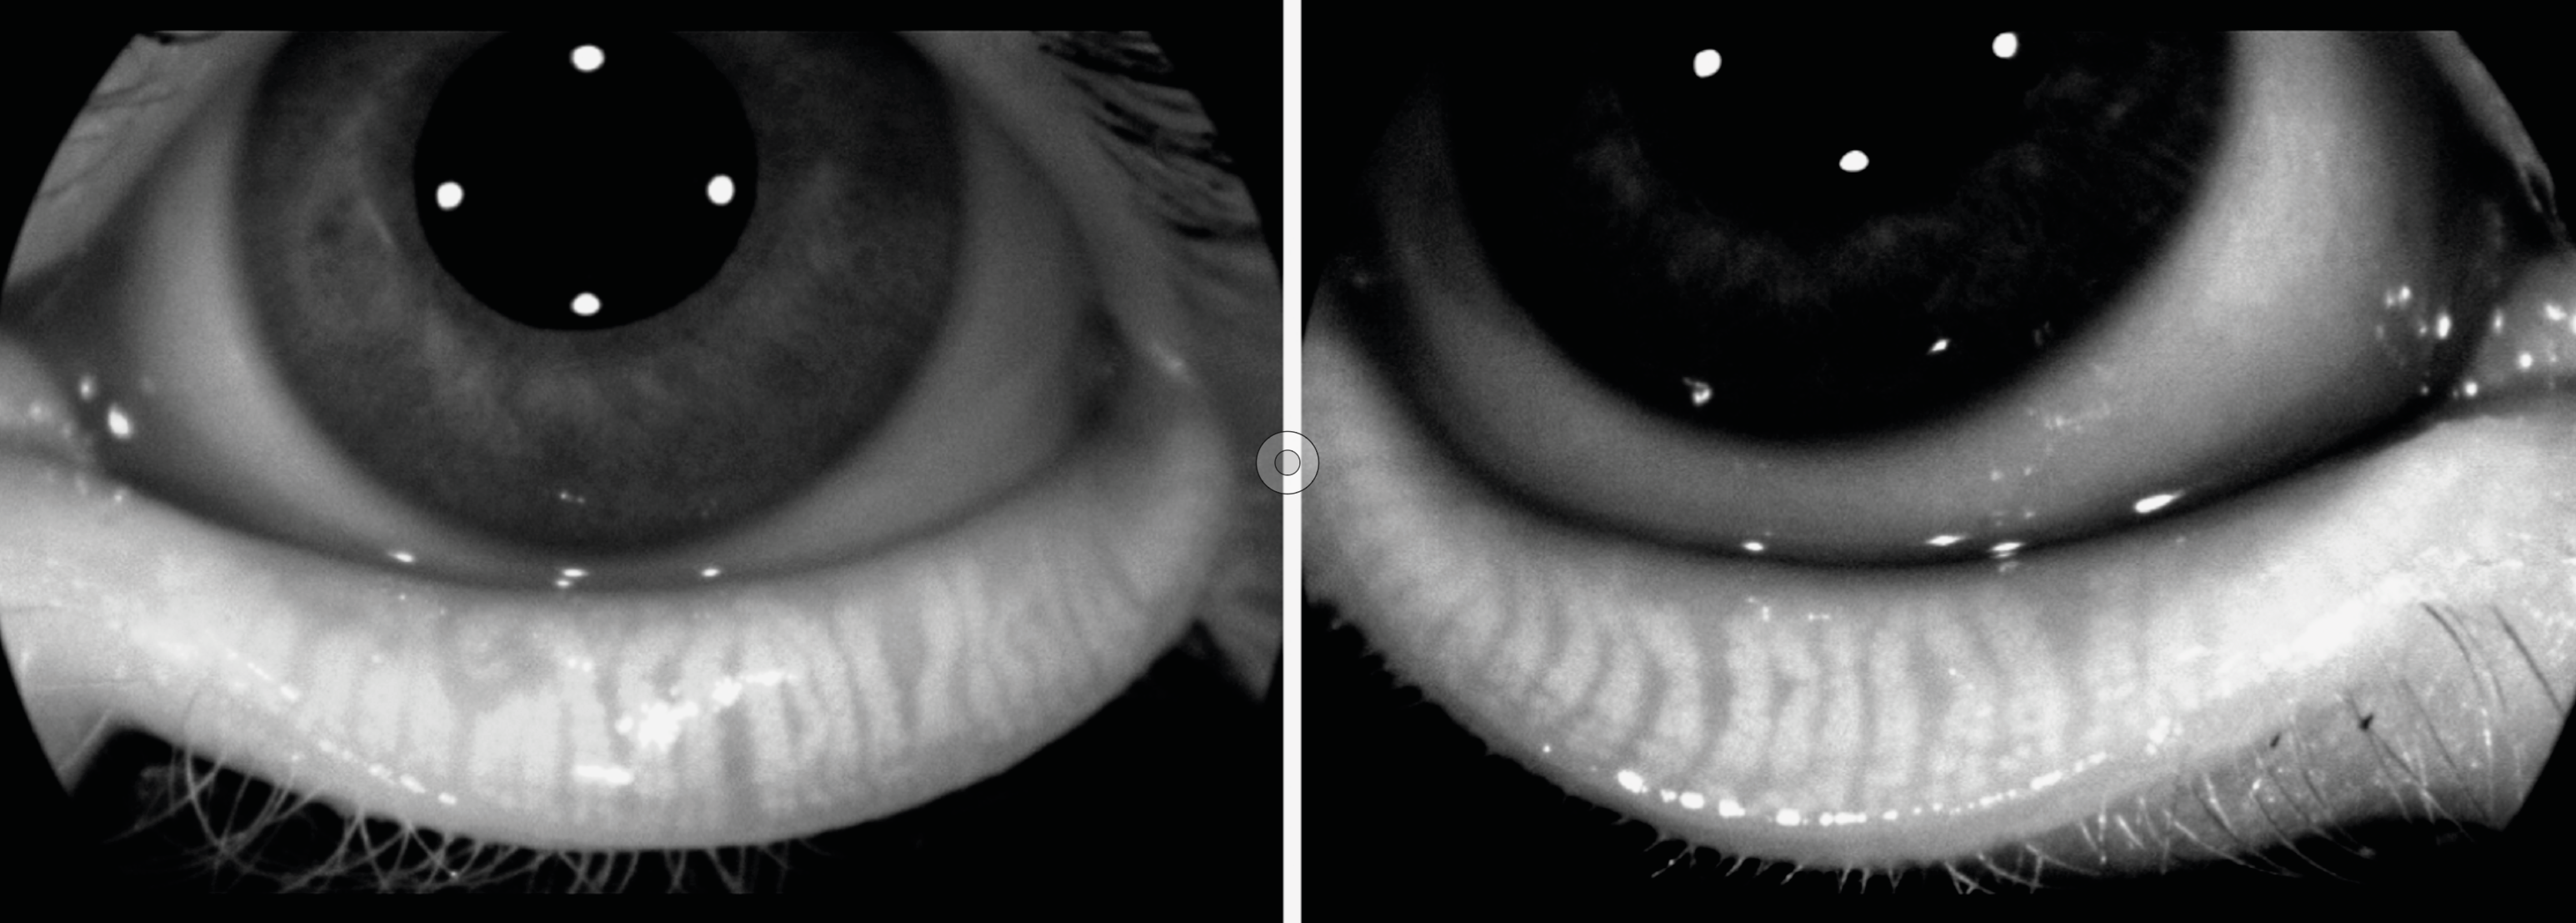

Figure 2. A. OCT RNFL initial OD/OG objectivant une atrophie temporale bilatérale.

Figure 2. B. OCT RNFL à 3 mois d’évolution OD/OG témoignant d’un amincissement diffus du RNFL ODG malgré la supplémentation initiée.